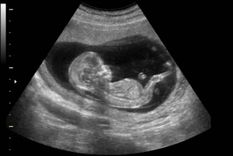

proyecto de ley de Detección del Latido Cardíaco Fetal